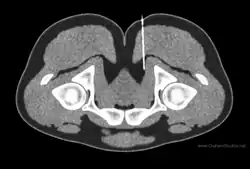

Illustration of imaging from a CT-guided nerve block. The needle tip has been placed at the top of the pudendal canal to block the pudendal nerve.

Diagnostic nerve blocks are very effective for identifying sensory entrapment points. Their strength is that they can directly measure whether a given nerve is contributing pain, or not. They are precise and reproducible.[36] As successful blocks require accurate targeting of the nerve, this is done under image guidance such as fluoroscopy, ultrasound,[37] CT,[37] or MRI.[38] Ultrasound is popular choice because of its soft-tissue contrast, portability, lack of radiation, and low cost, but is not good at depicting deeper structures like the deep pelvic nerves. For deeper structures, CT and MRI are more appropriate, although the equipment is more expensive.[39][40][41][37][38]